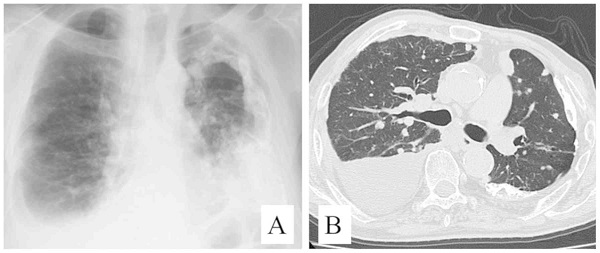

甲状腺乳頭癌 肺転移 CT画像。中-下肺野に、小粒状陰影が多数あります。

甲状腺癌の肺転移様式として、両側肺に、びまん性多発小結節を形成するのが普通です(上記肺X-p、CT画像)。孤立結節型は11.4%とされます。

甲状腺乳頭癌の孤立性肺転移CT・PET-CT画像[Thorac Cancer. 2016 Mar;7(2):261-3.]